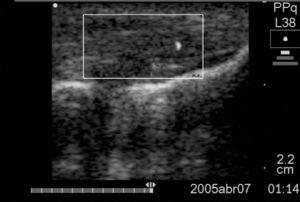

Tots 2 pacients presentaven engrossiment del tendó amb pèrdua del patró fibril·lar, zones hipoecoiques i neovascularització en els terços proximal i mitjà del tendó (figura 1).

Figura 1 Tall longitudinal del tendó del cas 2 que mostra l'engrossiment, les àrees d'hipoecogenicitat i la neovascularització.

Figura 2a Tall longitudinal del tendó del cas 1 previ a la primera esclerosi amb neovascularització +3.